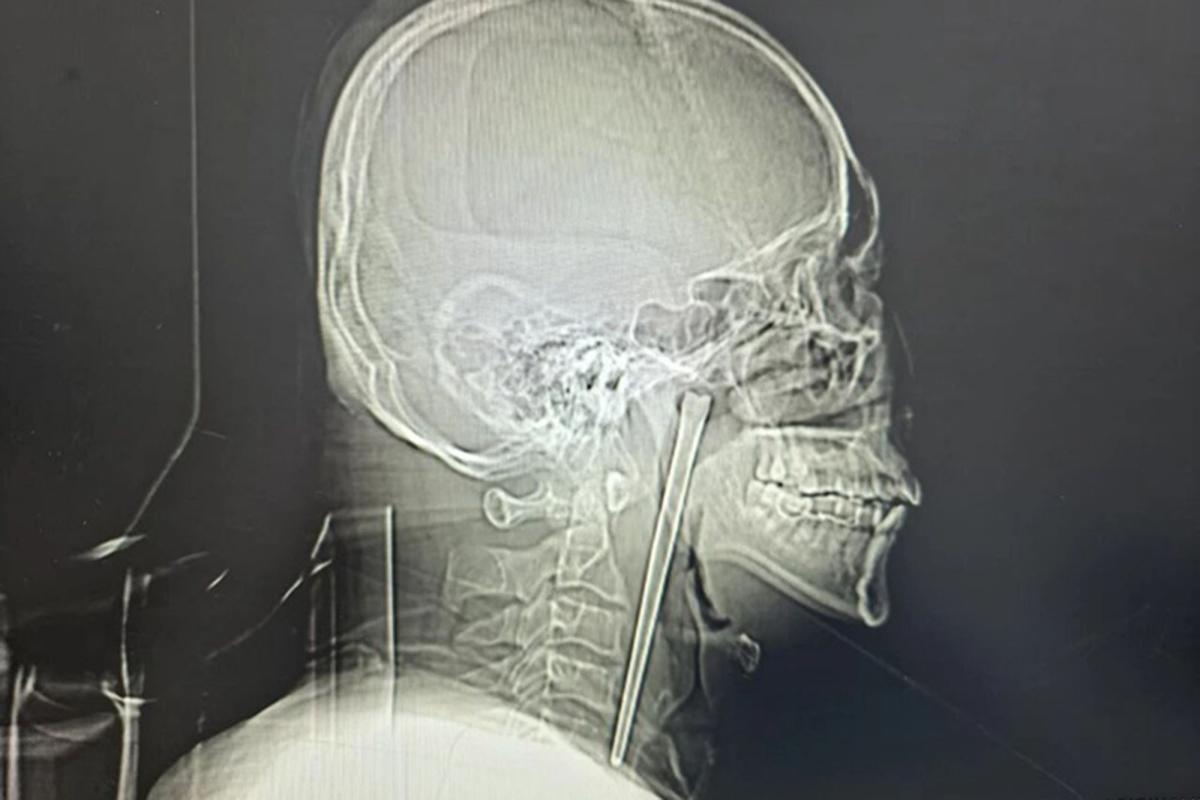

A man in China swallowed a metal chopstick while eating dinner eight years ago and decided to leave it lodged in his throat until a surgeon finally removed it last month, March 2026.

According to a jaw-dropping hospital case study published in March, the “alcoholic” patient, identified only as Mr. Wang, went in for a check-up shortly after gulping down the five-inch utensil in 2018 but refused to have it removed.

Wang, 46, didn’t want doctors to cut his neck open at the time, so he lived with the discomfort for years, the South China Morning Post reported.

Surgeons performed a minimally invasive operation to remove the obstructive object via Wang’s mouth instead of slicing open his neck, according to the hospital’s report.